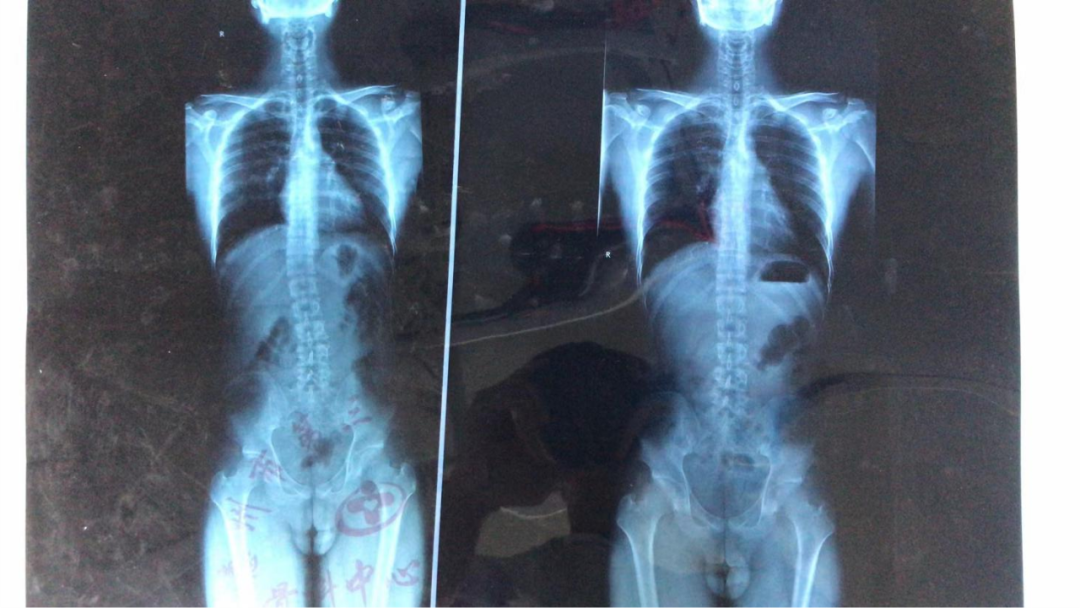

治療前側(cè)彎30度,配合矯形支具治療后側(cè)彎剩余18度